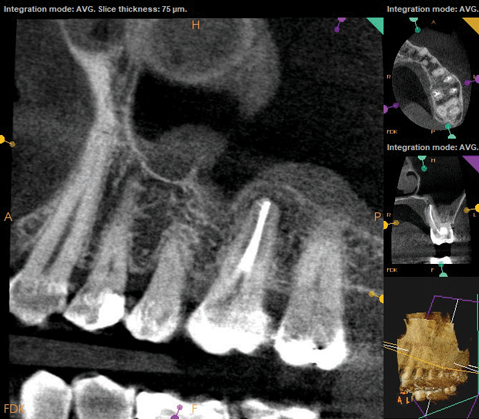

A 52-year-old male patient was seen by his otolaryngologist for symptomatic and unilateral sinusitis of 6 months duration. Medical CT showed dental pathology (Figure 5). His general dentist had a bitewing radiograph on file and referred the patient for endodontic evaluation (Figure 6).

As part of the endodontic evaluation, CBCT imaging showed periapical pathology associated with tooth No. 14 as well as significant MSEO (Figure 7 and Figure 8). Clinical testing confirmed the absence of a cold response but no tenderness to percussion or palpation. A composite buildup was in place, absent evidence of recurrent decay. Soft tissues were unremarkable.

Fig 5. Case 2. Preoperative CT imaging from otolaryngologist showing periapical radiolucency associated with tooth No. 14 and associated maxillary sinus mucositis.

Figure 5

Fig 6. Preoperative bitewing imaging from general dentist.

Figure 6

Fig 7 and Fig 8. Preoperative CBCT scans showing evidence of periapical pathology on tooth No. 14 as well as communication with the adjacent maxillary sinus and associated mucositis. Fig 7: Sagittal view, buccal roots No. 14. Fig 8: Sagittal view, palatal root No. 14.

Figure 7

Fig 8. Preoperative CBCT scans showing evidence of periapical pathology on tooth No. 14 as well as communication with the adjacent maxillary sinus and associated mucositis. Fig 7: Sagittal view, buccal roots No. 14. Fig 8: Sagittal view, palatal root No. 14.

Figure 8